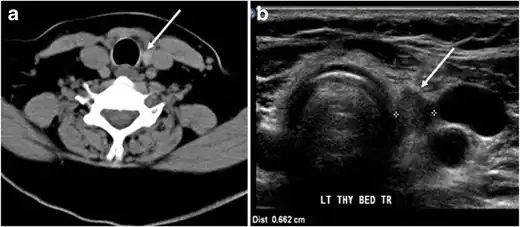

Fig. 7. A 51-year-old female patient post total thyroidectomy for PTC with elevated thyroglobulin measurement. an Axial non-enhanced CT scan of the neck at the level of the thyroid bed demonstrates a well-defined, rounded, homogenously dense soft tissue situated between the trachea and left internal jugular vein (white arrow). b Transverse ultrasound image of the neck demonstrates a well-defined, homogeneous, hypoechoic soft tissue nodule measuring 6 mm (white arrow) with no detected micro-calcifications. Biopsy showed a predominantly residual normal thyroid tissue with micro-foci of PTC.[1] -

Fig. 8. A 48-year-old male patient post total thyroidectomy with PTC recurrence. a Transverse greyscale ultrasound of the neck demonstrates a left thyroid bed heterogeneous, predominantly hypoechoic irregular lesion with calcifications (white arrow). b A spot image of iodine 123 total body scan of the neck demonstrate a focus of abnormal radiotracer uptake at the left thyroid bed (Black arrows) between the annotated markers. c Enhanced axial CT scan of the neck demonstrates an enhancing large left thyroid bed mass (white arrow) with no calcifications. The lesion exerts a mass effect on the oesophagus (black arrow) and is inseparable from the trachea.[1] -